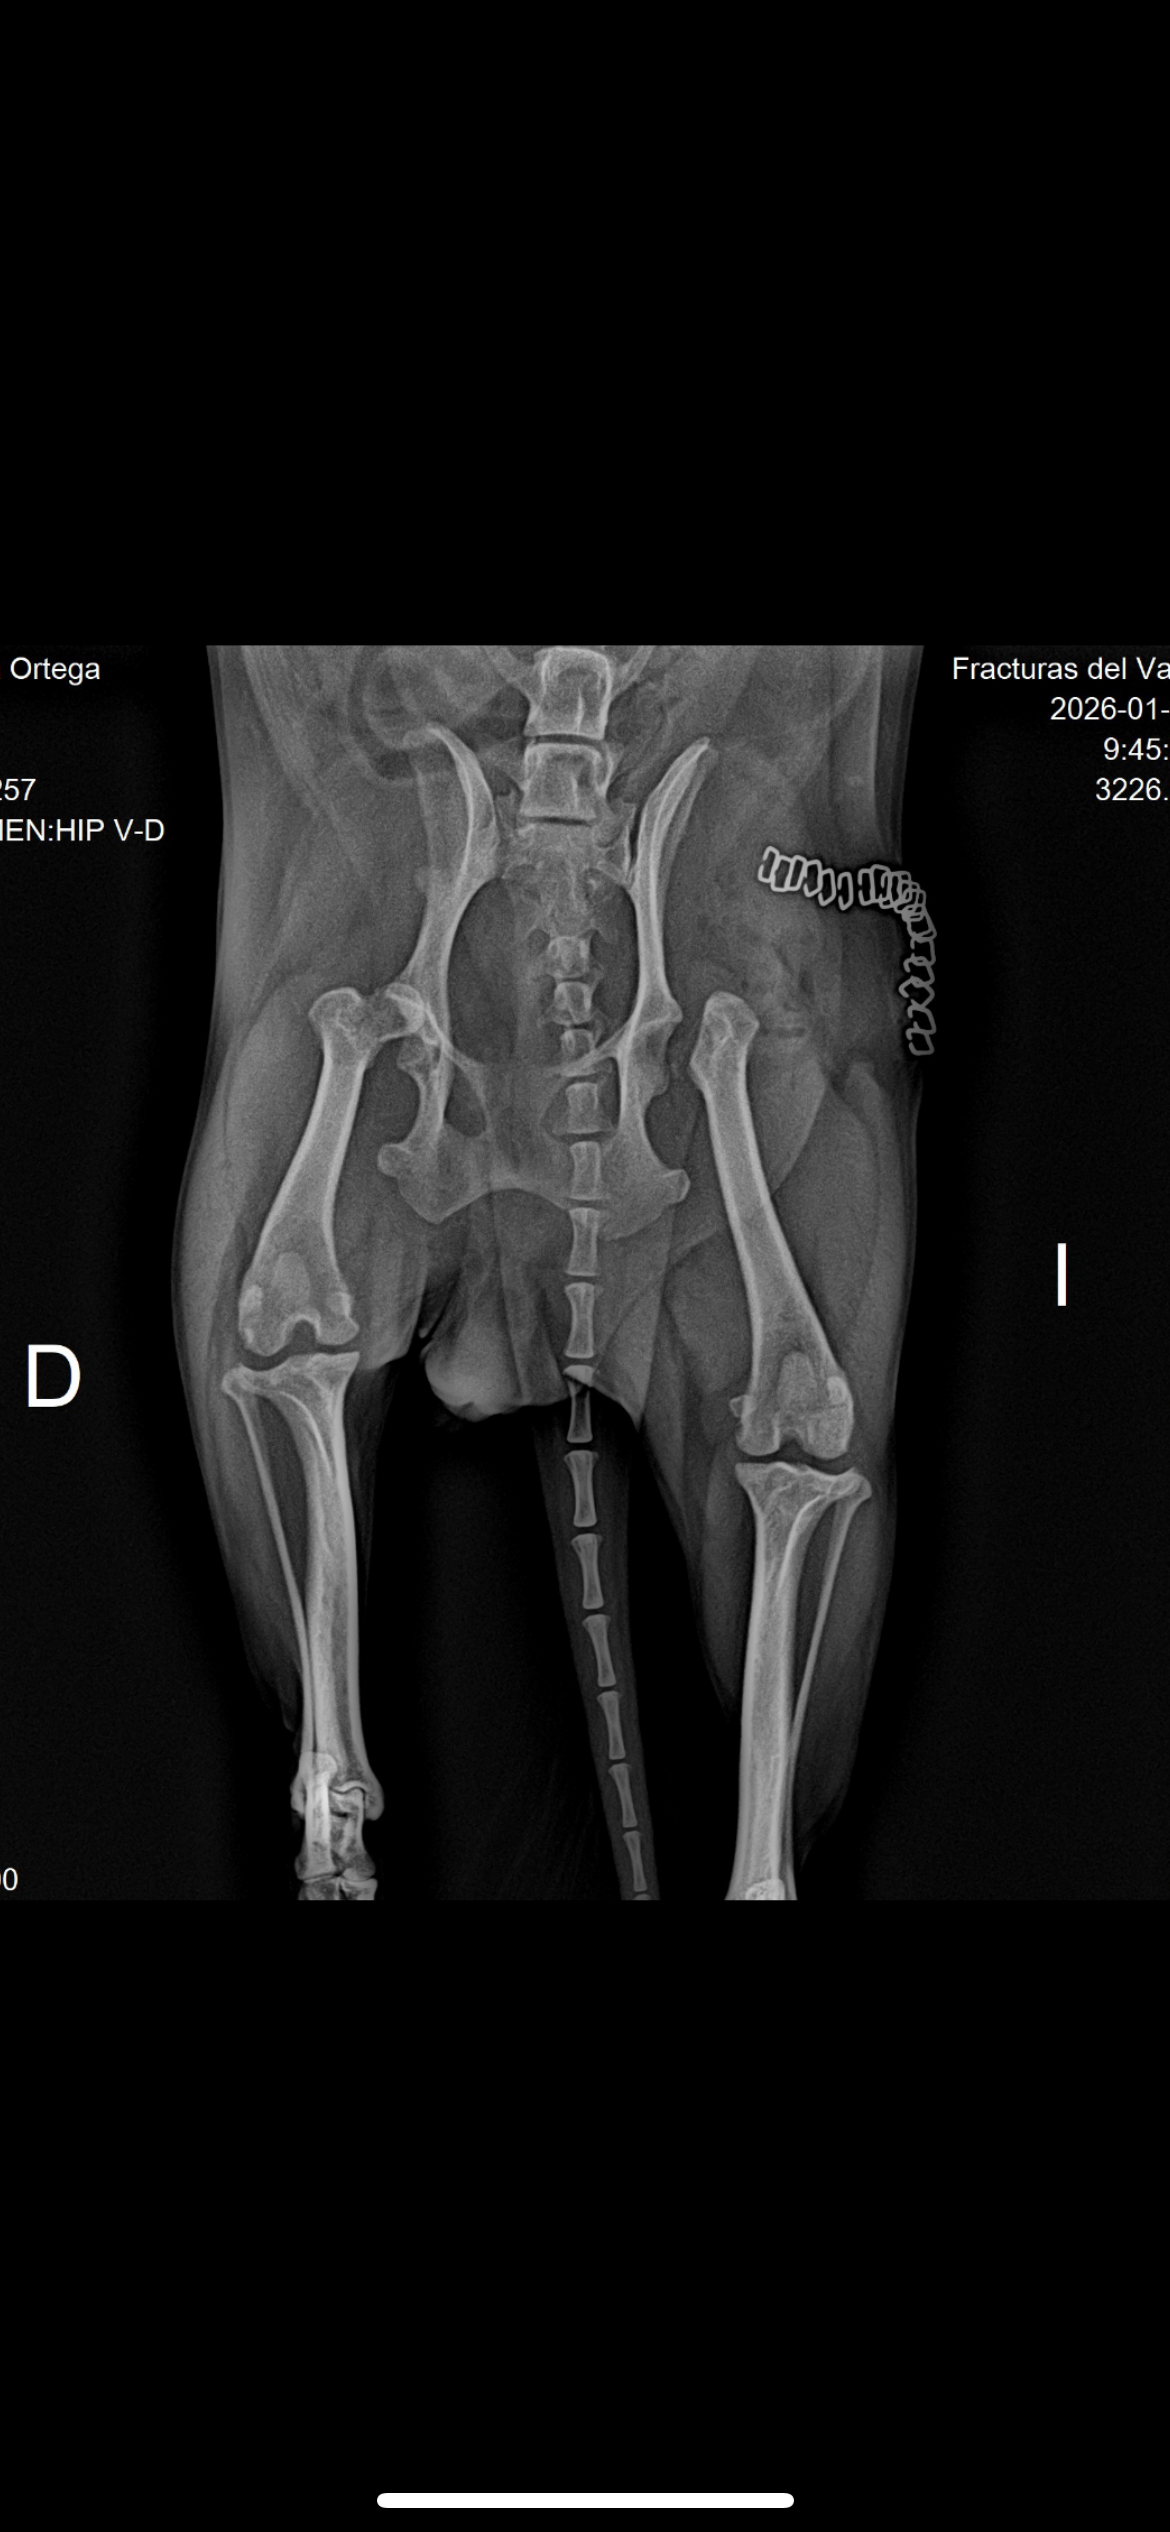

Ginebra es una perrita pequeña, con alma de niña y hoy está enfrentando algo muy grande.Tiene una condición compleja que provocó que sus dos paticas se dislocaran de la cadera, causándole dolor constante y limitando su movilidad. La única opción para darle una mejor calidad de vida es una cirugía de ablación bilateral, un procedimiento duro, invasivo y con un posoperatorio largo y delicado para cualquier perrito.

Vamos piernita por piernita; Cada una implica cirugía, medicamentos, exámenes, controles y mucho cuidado, el costo aproximado es de 1.000 euros por pierna, y aunque hago todo lo que está a mi alcance, esta vez no puedo sola.